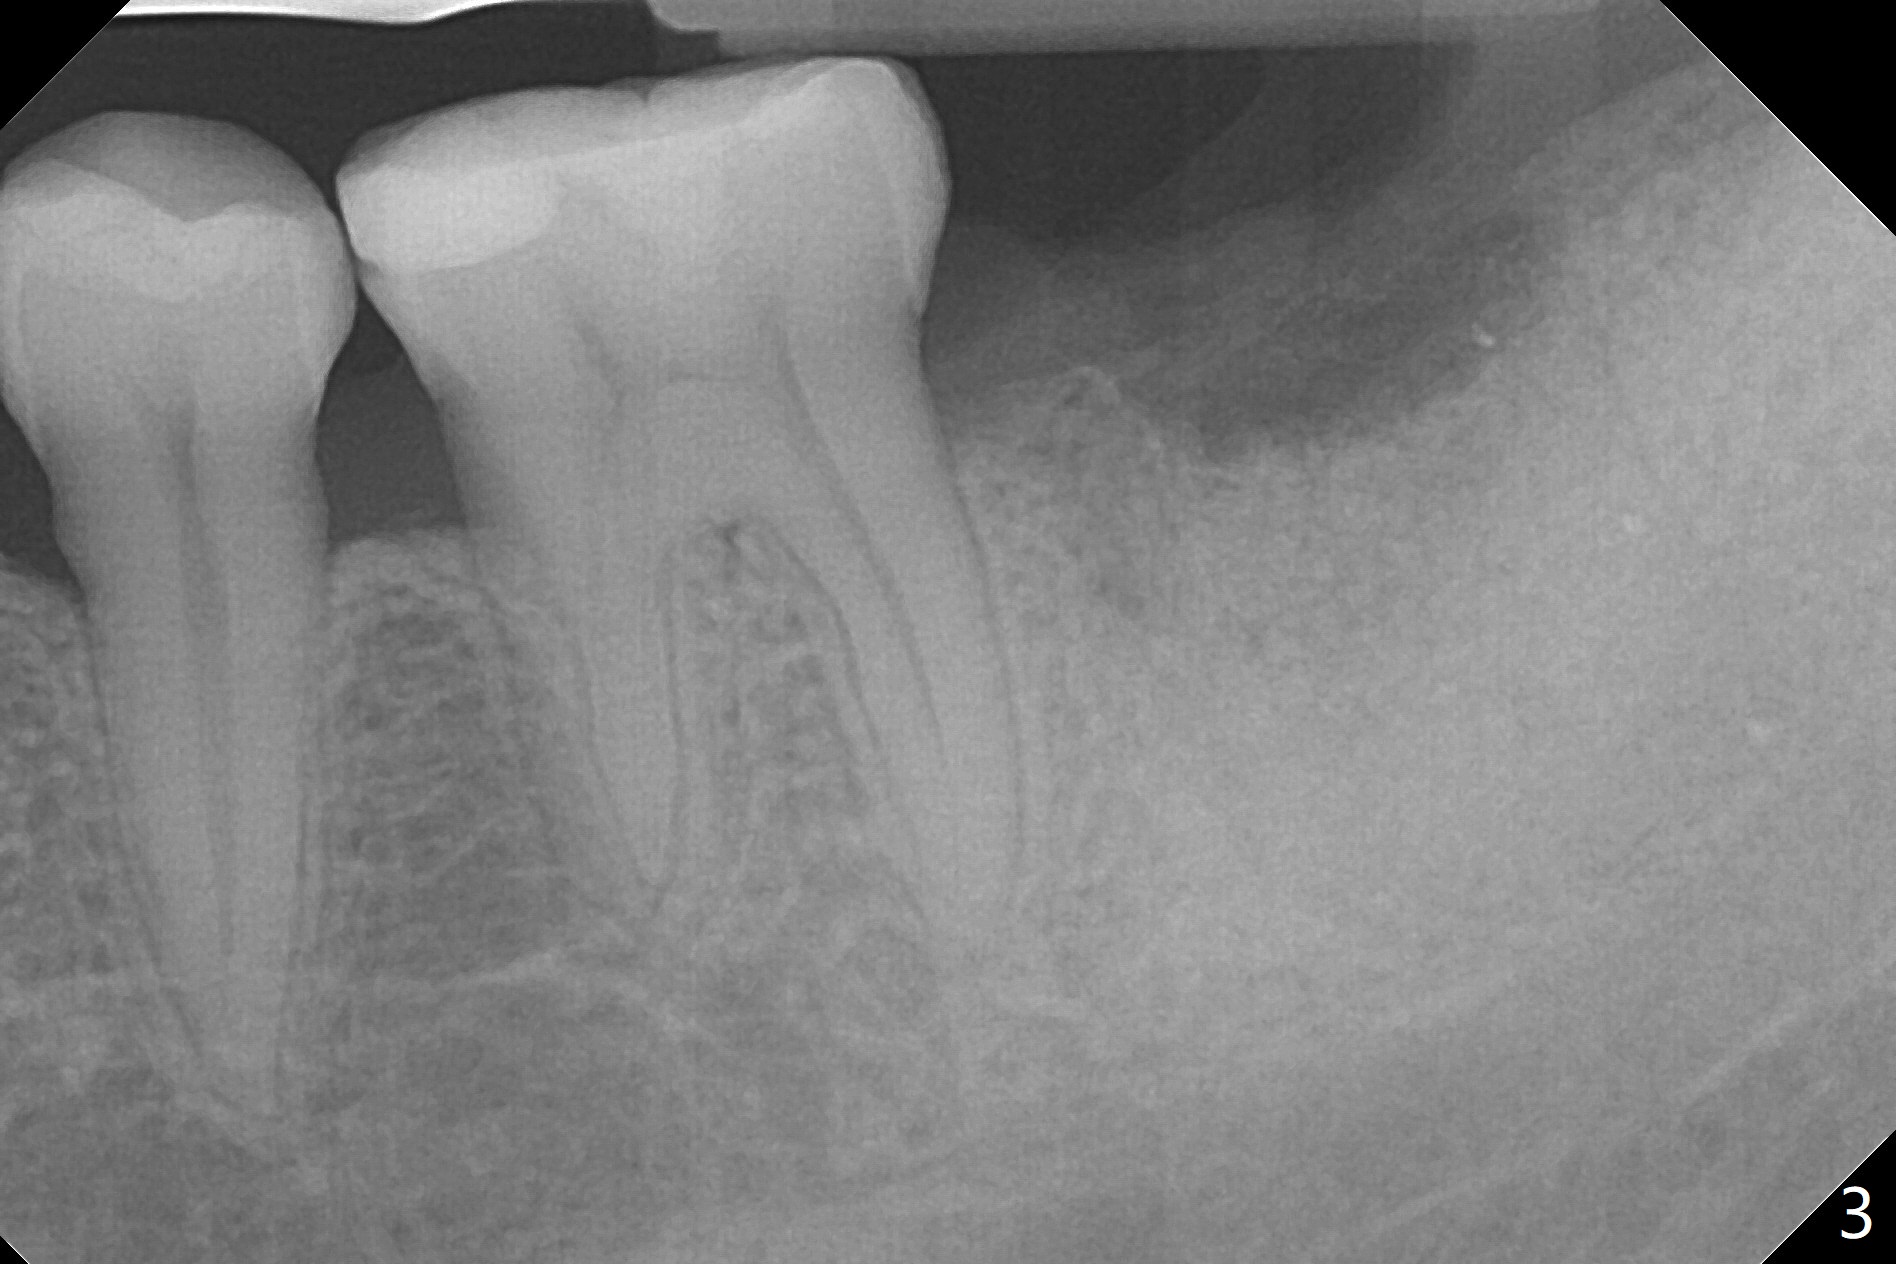

The patient with chronic buccal abscess at #31 is nervous.  After extraction, a 7x11 mm tapered implant drops into the single socket, which is close to the Inferior Alveolar Canal (Fig.2).  The bottom of the socket is sensitive to manipulation (explorer) after infiltration anesthesia.  A 8x14 mm tapered tap is placed without binding, neither is a 8x14 mm cylindrical implant.  The implant stability does not increase when Vera (.2-1.0 mm) or Vanilla (.5-1.0 mm) Graft is placed.  Socket preservation is finished with Collagen plug and 6-month membrane (Fig.3,4).